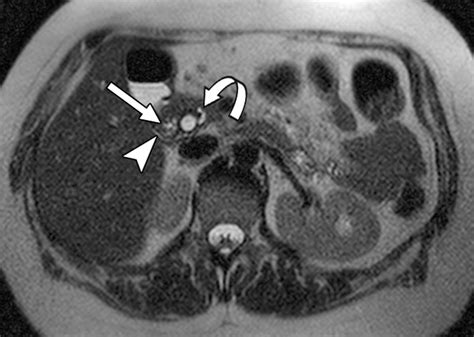

• Density and Texture: Normal pancreatic tissue has a specific density. Areas that appear brighter or darker than the surrounding tissue—known as hypoattenuating or hyperattenuating lesions—often warrant further investigation.

• Ductal Dilation: The pancreatic duct, which carries enzymes to the intestines, should ideally remain narrow. If this duct is dilated, it could suggest a blockage caused by stones, scarring, or a mass.

• Surrounding Fat Stranding: In cases of inflammation, the fat surrounding the pancreas often appears "strandy" or hazy on the scan, which is a hallmark sign of pancreatitis.